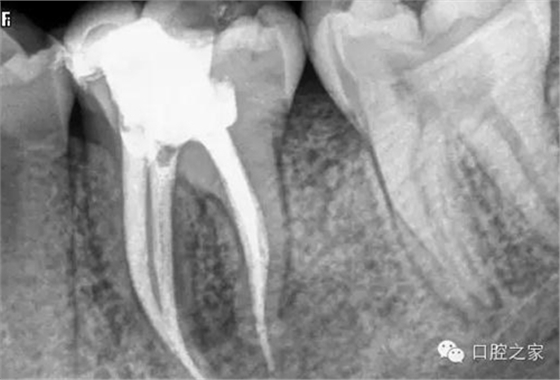

蘸一般藥液的棉捻或紙尖X 線片難以顯影,只有在根尖切除或拔除患牙后才能確診。但蘸有碘仿等X線阻射藥物的棉捻在照片上則易顯影(圖3)。此外,行樁冠修復(fù)的患牙,在釘?shù)李A(yù)備時(shí)如操作失誤,也可將牙膠尖推出根尖孔,導(dǎo)致治療失敗。